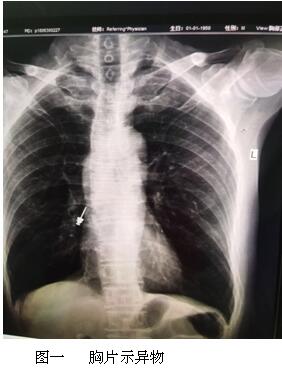

步步驚心的異物

六月最后一天的上午,內(nèi)鏡中心來了一名特殊的患者,患者表情焦慮,訴于外院補(bǔ)牙時(shí),不小心把補(bǔ)牙的一顆螺絲吞下,現(xiàn)咽喉部明顯不適,于我院耳鼻喉行喉鏡檢查,未見明顯異物,內(nèi)鏡中心伍友興主任聽聞后,考慮異物可能卡在食管上段,持鏡給予患者行胃鏡檢查,但是反復(fù)觀察食道、胃及十二指腸,并未找到患者所描述的異物。是不是有可能異物已經(jīng)掉入十二指腸以下的消化道了呢?如果已經(jīng)掉入小腸,這一顆大約長(zhǎng)2cm的螺絲,表面無明顯銳利邊緣,刺破腸管的可能性較小,可自行隨大便排出,正當(dāng)我們準(zhǔn)備松一口氣告訴患者胃鏡下未見明顯異物時(shí),患者輕輕的咳嗽兩聲引起了伍主任的注意,“快去行胸部照片,異物可能掉入氣管”伍主任說到,患者遂行胸部照片,見異物果然出現(xiàn)在患者右側(cè)的肺里,為進(jìn)一步確定異物部位,給予行胸部CT檢查,并積極聯(lián)系呼吸內(nèi)科豐偉民主任,黃雪英老師與豐主任兩人密切配合,在支氣管鏡下看到右側(cè)支氣管下段,找到了讓人揪心的異物,順利取出,此刻患者緊縮的眉頭終于舒展開來,連連向我們醫(yī)務(wù)人員道謝。